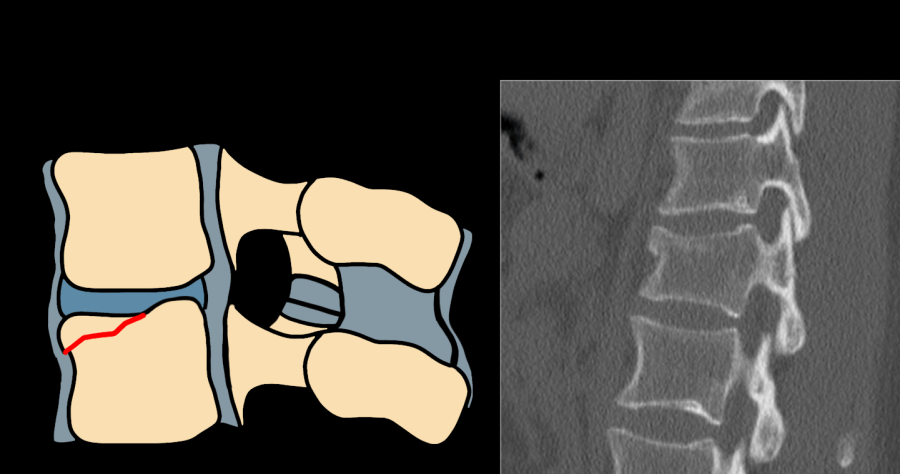

AO Type B3 hyperextension injury — diagram and CT showing anterior tension band disruption through disc with anterior column distraction

Type B3 — hyperextension injury; anterior tension band disruption